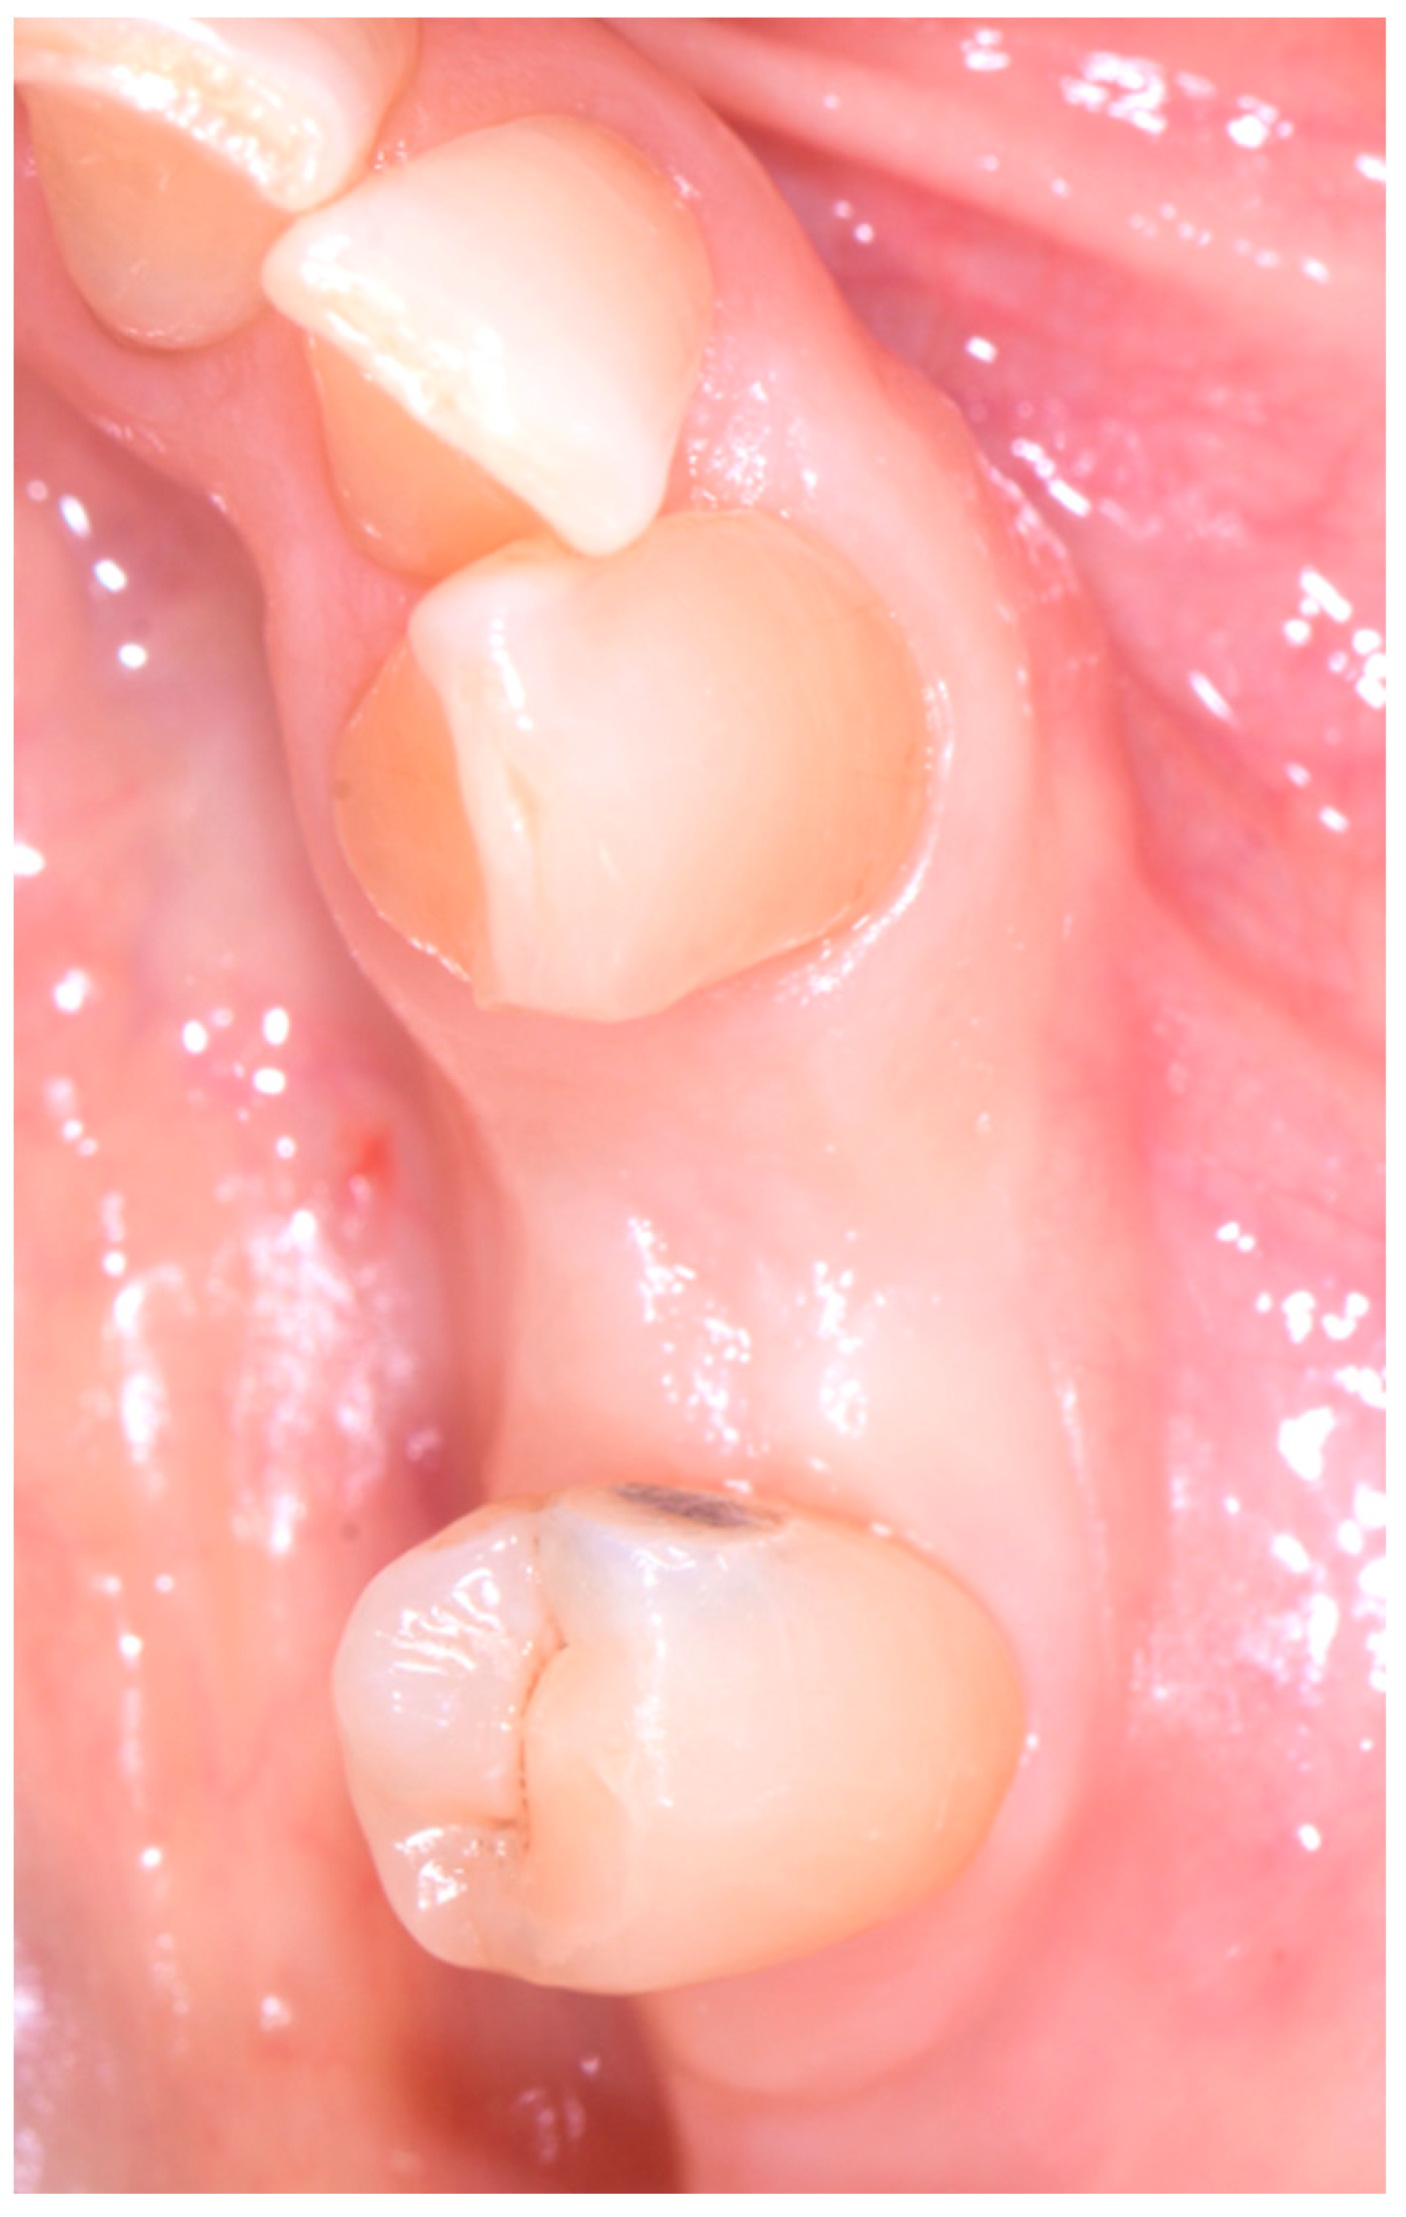

The following case study report was performed in the private clinic Dott. A Grassi, in compliance with the patient who satisfied the inclusion criteria and was included in the present study: male, 62 years old, not a smoker, and in general good health. Written informed consent was signed by the patient for the clinical procedure and for the present study. The patient was provided with a prophylaxis starting the day before the surgery for 6 days, with 2 g of amoxicillin and clavulanic acid. Pre-operative CBCT with a Carestream 8100 3D (Carestream Dental, Atlanta, GA, USA) was performed (Figure 1a–c).

Subsequently, an incision of the papillae was made using a #15c surgical scalpel with a full-thickness envelope flap. A fenestration was observed on the buccal bone, the lingual–buccal length was approx. 8.3 mm.

Figure 1. CBCT images of the patient before the surgery: (a) frontal section, (b) transversal section, and (c) sagittal section.